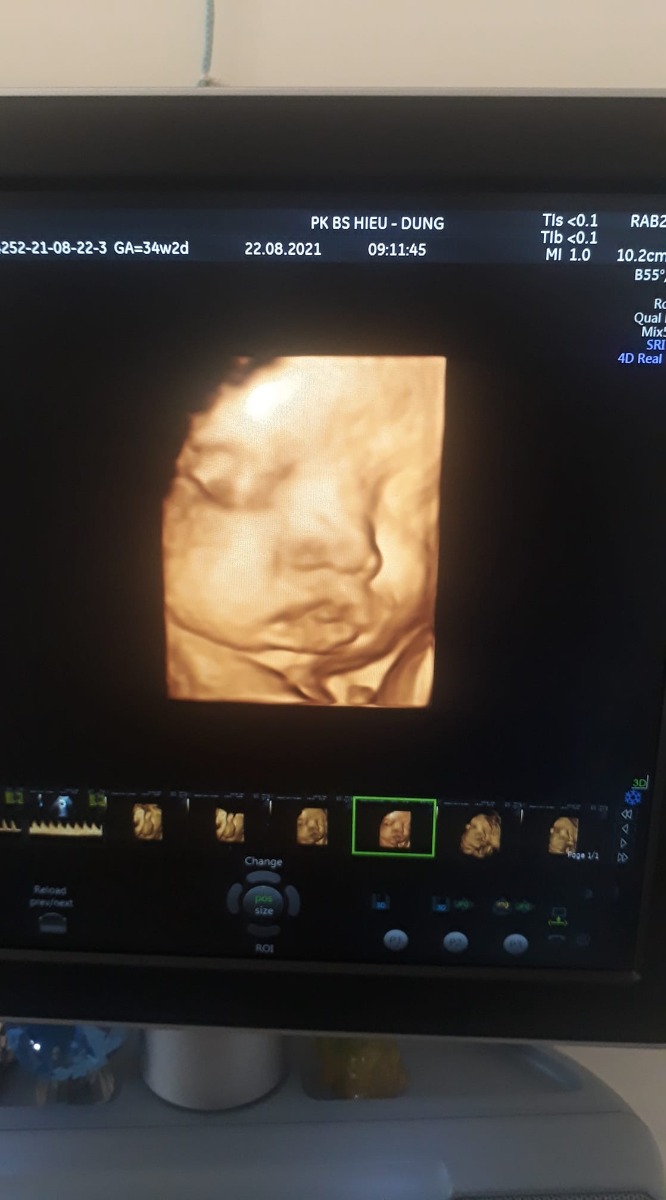

Vào đến phòng siêu âm, khoảnh khắc nghe đc nhịp tim của em,mẹ lại khóc.Em đã ở lại với mẹ.

Cũng có khi vì lo lắng nên giờ 36w mẹ mới lên có 3kg,tv em bé của mẹ phát triển khỏe mạnh.Chỉ còn 2 tuần nữa mẹ con mình gặp nhau rồi.Mong em bé của mẹ ngoan ngoãn chờ ngày ra với mẹ.